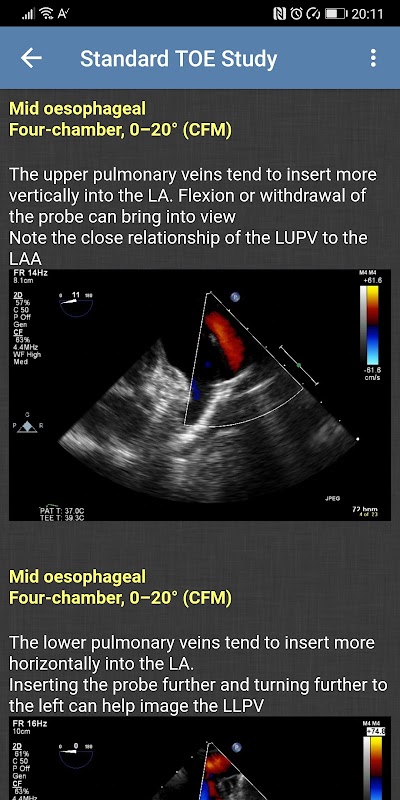

- Studi TOE Standar